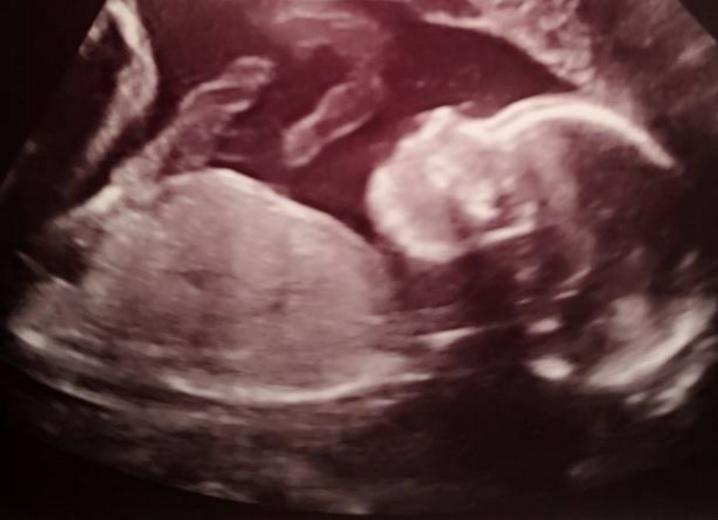

Un bebeluș se va naște de două ori! Medicii l-au scos din pântece și apoi l-au pus înapoi - Foto | Imaginea 2 din 2 | Galerie Foto

Un bebeluș se va naște de două ori! Medicii l-au scos din pântece și apoi l-au pus înapoi - Foto Un bebeluș se va naște de două ori! Medicii l-au scos din pântece și apoi l-au pus înapoi - Foto